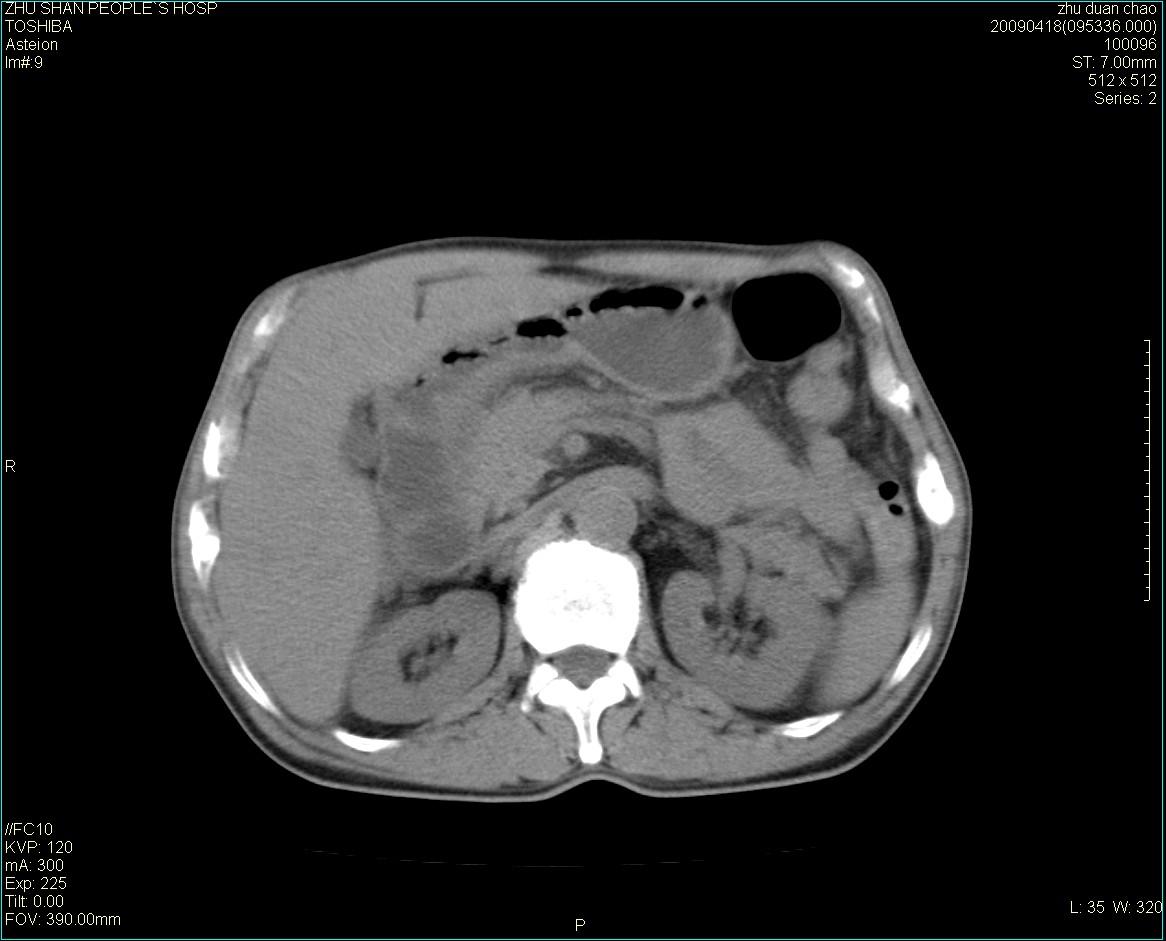

以下是引用余辉在2009-4-22 10:48:00的发言:[br]结肠肝曲附近肠段包块,病灶密度不均匀,周围肠系膜脂肪混浊,见多枚淋巴结肿大,考虑结肠癌可能性大,病灶累及范围较广建议进一步检查除外其他

以下是引用随光逐影在2009-4-22 11:57:00的发言:[br]考虑肠道肿瘤(间质瘤?)可能性大。

以下是引用ydx_74在2009-4-22 14:39:00的发言:[br]结肠癌周围侵犯可能,不能完全除外炎性病变